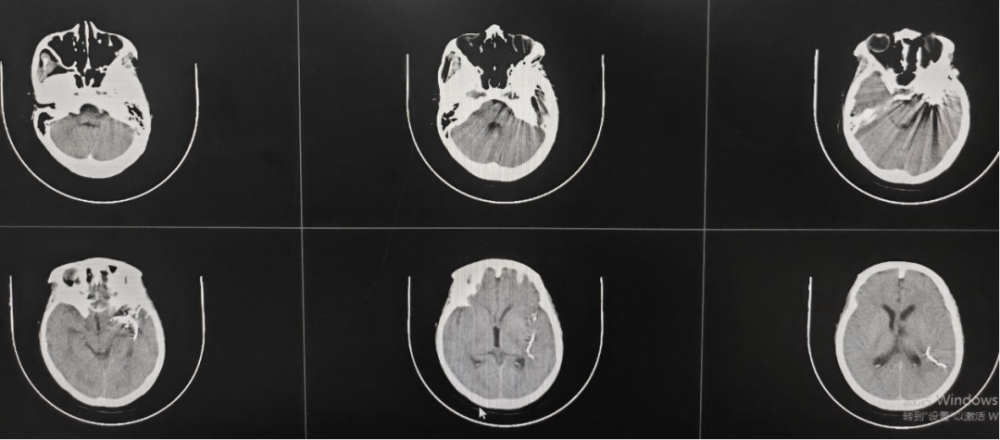

术后CT

术中,在纪文军主任医师、张伟副主任医师、李涛副主任医师、赵乐副主任医师及麻醉手术科团队的紧密协作下,成功对王女士脑中的动静脉畸形多支供血血管进行了栓塞。手术历时两个多小时,顺利完成。术后复查脑血管造影显示,颅内动静脉畸形已完全栓塞。后期经过神经外科二病区医护团队精心的康复治疗与护理,王女士恢复良好,意识清晰,已能正常生活和工作。